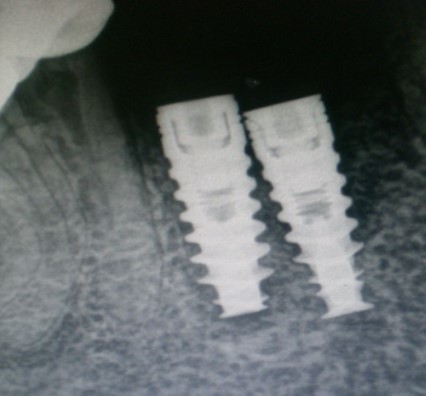

Unplanned implant placement or change in angulations of the implants due to anatomic limitations3,4 such as mandibular canal, mental foramen, nasal floor, sinus cavities or roots of the adjacent teeth, might result in close approximation of the implants (Figure 1), which poses tough challenges to the restorative dentist, who have to overcome certain technical difficulties for the fabrication of the prosthesis including making of a proper impression.

Figure 1.Radiograph – closely positioned implants.

Radiograph – closely positioned implants.

The other impression coping was modified by holding it with artery forcep and cut it with carborundum disc so that it fits properly over the other implant. After modification, it was secured with long connecting/fastening screw to the respective implant. the complete seating of the impression copings was verified with a periapical radiograph.